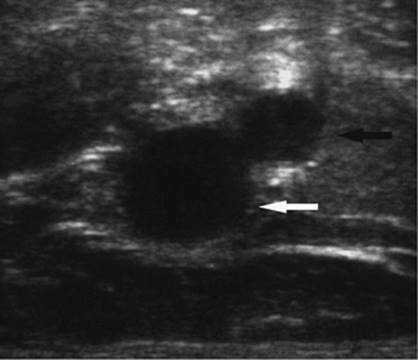

Figure 35.6. Ultrasound image showing typical appearance for thoracentesis guidance. The central target (pleural effusion) is identified by an asterisk, lung margin by arrowheads, and drainage catheter pathway with an arrow.